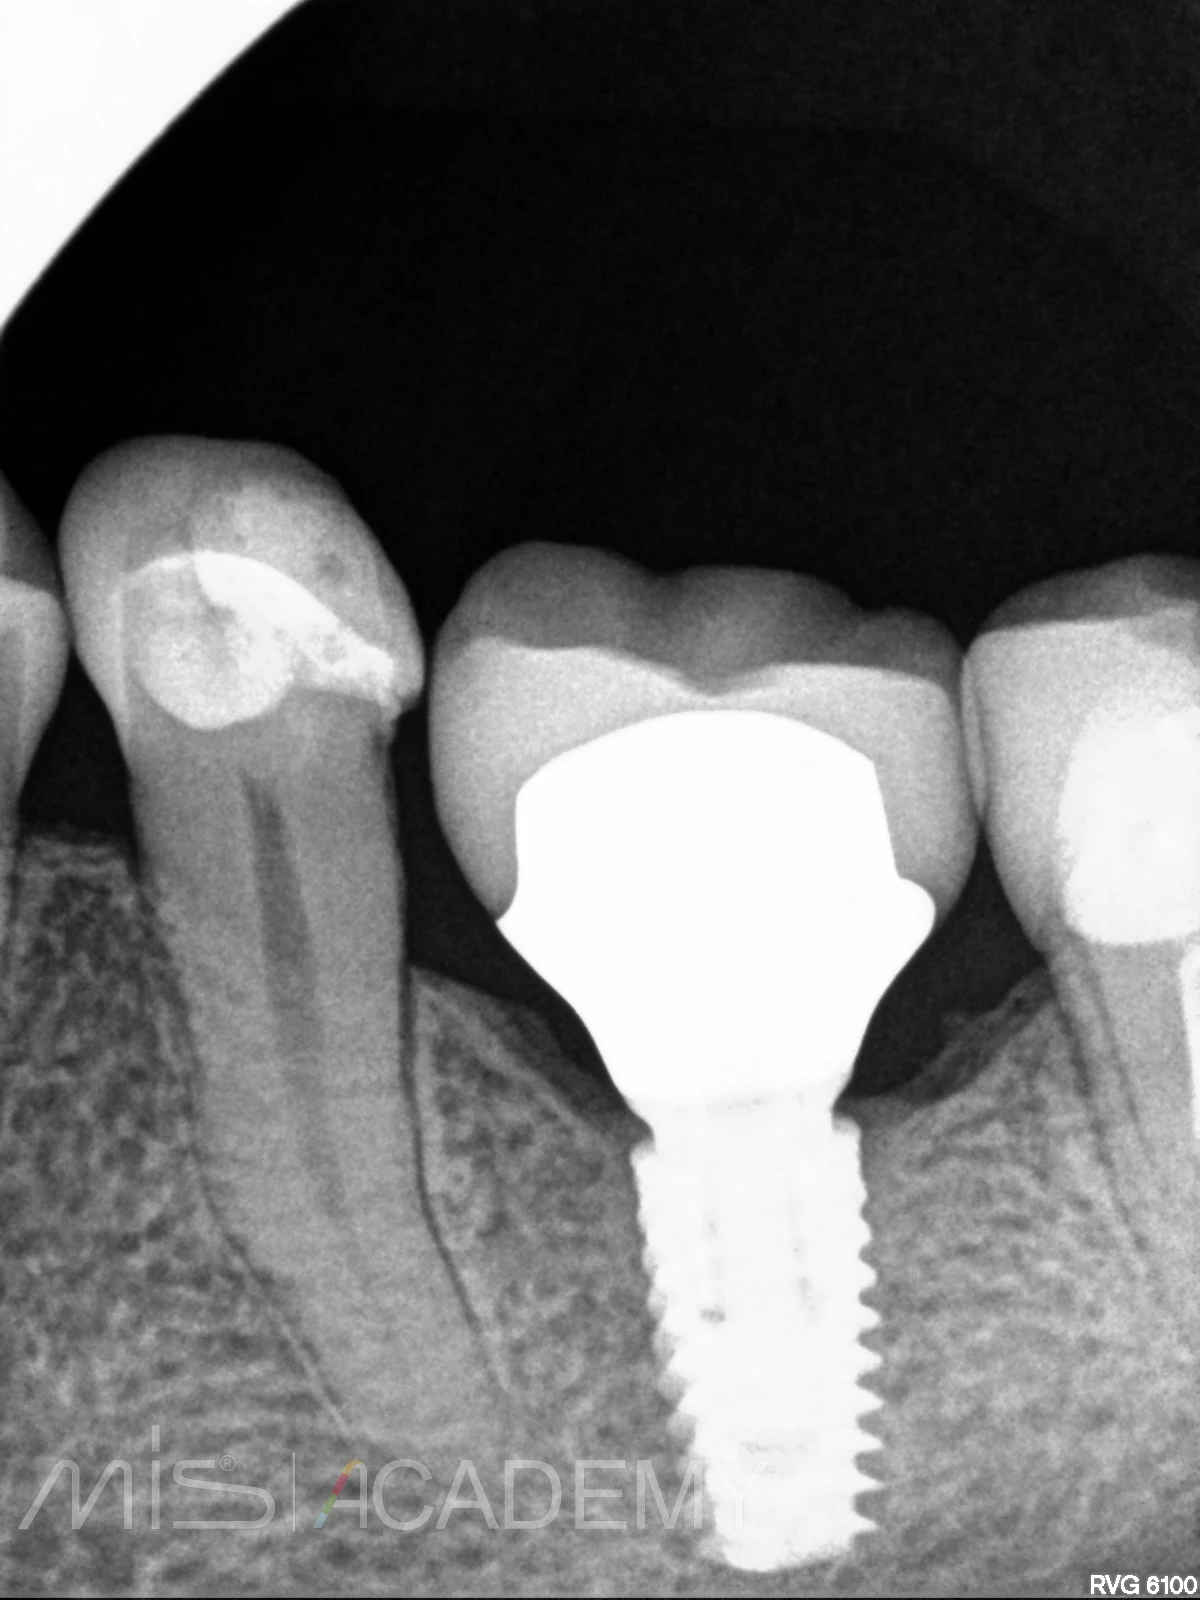

— Дистальный моляр тоже покрыли коронкой из дисиликата лития, а вот премоляр пациентка отказалась (На рг снимках ситуация после фиксации и через 2 года. Вроде как даже кортикализация произошла.